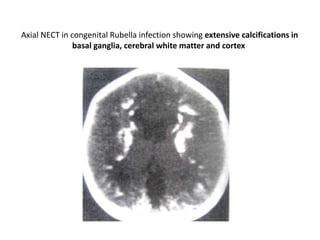

Axial NECT in congenital Rubella infection showing extensive calcifications in

basal ganglia, cerebral white matter and cortex

Axial NECT incongenital Rubella infection showing extensive calcifications in basal ganglia, cerebral white matter and cortex